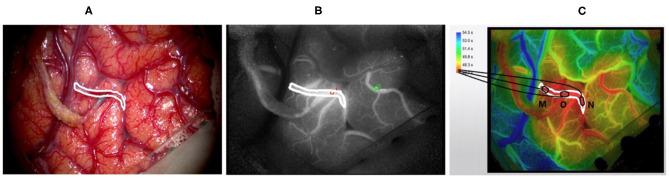

Microvascular imaging based on indocyanine green is an important tool for surgeons who carry out extracranial-intracranial arterial bypass surgery. In terms of blood perfusion, indocyanine green images contain abundant information, which cannot be effectively interpreted by humans or currently available commercial software. In this paper, an automatic processing framework for perfusion assessments based on indocyanine green videos is proposed and consists of three stages, namely, vessel segmentation based on the UNet deep neural network, preoperative and postoperative image registrations based on scale-invariant transform features, and blood flow evaluation based on the Horn-Schunck optical flow method. This automatic processing flow can reveal the blood flow direction and intensity curve of any vessel, as well as the blood perfusion changes before and after an operation. Commercial software embedded in a microscope is used as a reference to evaluate the effectiveness of the algorithm in this study. A total of 120 patients from multiple centers were sampled for the study. For blood vessel segmentation, a Dice coefficient of 0.80 and a Jaccard coefficient of 0.73 were obtained. For image registration, the success rate was 81%. In preoperative and postoperative video processing, the coincidence rates between the automatic processing method and commercial software were 89 and 87%, respectively. The proposed framework not only achieves blood perfusion analysis similar to that of commercial software but also automatically detects and matches blood vessels before and after an operation, thus quantifying the flow direction and enabling surgeons to intuitively evaluate the perfusion changes caused by bypass surgery.

基于吲哚菁绿的微血管成像对于进行颅外 - 颅内动脉搭桥手术的外科医生来说是一项重要工具。在血液灌注方面,吲哚菁绿图像包含丰富信息,这些信息无法被人类或当前可用的商业软件有效解读。本文提出了一种基于吲哚菁绿视频的灌注评估自动处理框架,该框架由三个阶段组成,即基于UNet深度神经网络的血管分割、基于尺度不变特征变换的术前和术后图像配准以及基于Horn - Schunck光流法的血流评估。这种自动处理流程可以揭示任何血管的血流方向和强度曲线,以及手术前后的血液灌注变化。本研究中使用嵌入显微镜的商业软件作为参考来评估算法的有效性。总共从多个中心抽取了120名患者进行研究。对于血管分割,获得了0.80的Dice系数和0.73的Jaccard系数。对于图像配准,成功率为81%。在术前和术后视频处理中,自动处理方法与商业软件之间的符合率分别为89%和87%。所提出的框架不仅实现了与商业软件类似的血液灌注分析,还能自动检测和匹配手术前后的血管,从而量化血流方向,使外科医生能够直观地评估搭桥手术引起的灌注变化。